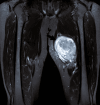

Figure 2

Figure 2. Axial T2-weighted MRI showing a hyperintense, well-defined mass in the thigh with surrounding edema.